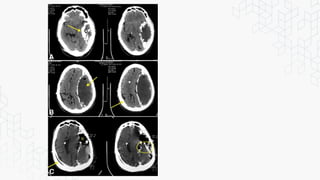

Tc de Enfermedad traumática

TC cerebro sin contraste corte axial

hematoma subdural agudo (flecha).

hematoma epidural.

TC de cerebro sin contraste:

Hemorragia subaracnoidea.

Tc de Enfermedadtraumática TC cerebro sin contraste corte axial hematoma subdural agudo (flecha). TC cerebro sin contraste corte axial hematoma epidural. TC de cerebro sin contraste: Hemorragia subaracnoidea.